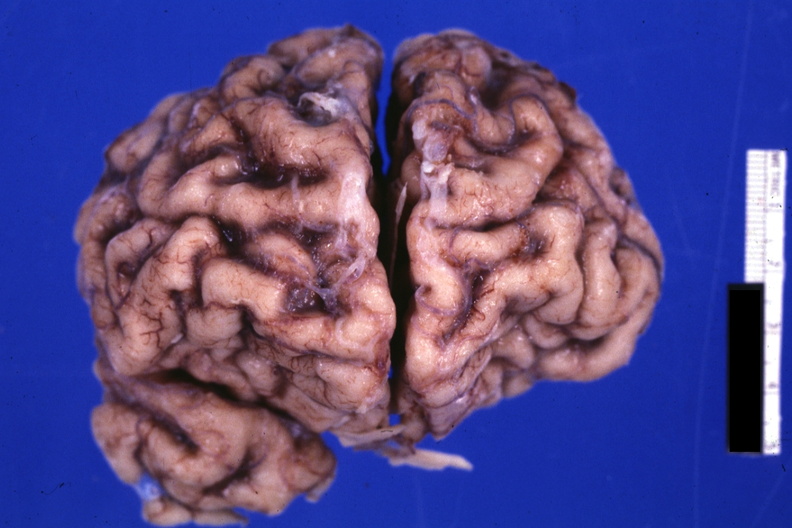

GROSS: NERVOUS: Brain: Cortical Atrophy: Gross fixed tissue frontal poles I think shown close-up with marked cortical atrophy good photo

- brain, cortical atrophy, gross, nervous